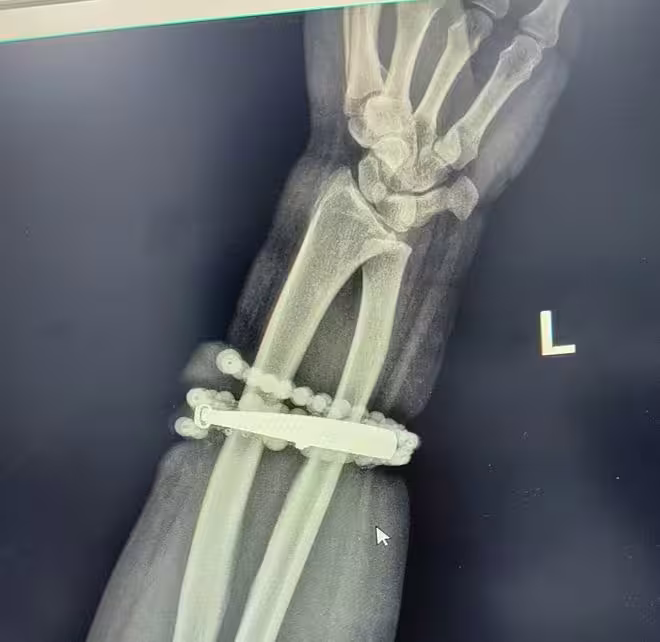

女子戴手鐲10年沒摘,竟「長」進了肉里!醫生:再晚點手就保不住了!

經過一個多小時的手術,醫生們將手鐲和串珠從厚厚的增生組織中完整剝離出來。目前,龔女士恢復良好,已順利出院。